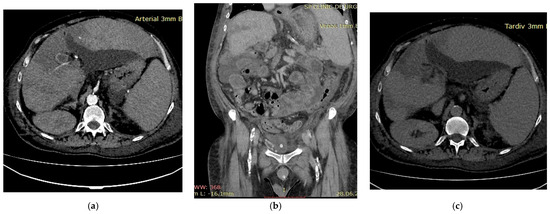

A 52-year-old male patient with decompensated alcoholic liver cirrhosis was admitted with progressive liver failure. His past medical history was notable for untreated diabetes and inherited thrombophilia due to Factor V Leiden mutation, diagnosed 20 years earlier following an acute myocardial infarction. Biological parameters indicated severe hepatic failure, hyperglycemia and elevated glycated hemoglobin, reflecting poor metabolic control and concomitant renal dysfunction. Multiphasic contrast-enhanced computed tomography revealed thrombosis of the portal venous system during the portal venous phase (Figure 3b). Arterial-phase imaging revealed reduced enhancement of segmental hepatic arterial branches supplying a centrally localized infarcted area (Figure 3a), while delayed images confirmed patency of the hepatic veins (Figure 3c), thereby excluding hepatic venous outflow obstruction. Anticoagulant therapy with low molecular weight heparin (LMWH) at a therapeutic dose, adjusted for renal function, was initiated, along with general measures to support organ function. The patient’s general condition deteriorated rapidly and he ultimately died. This case underscores several important clinical considerations. First, inherited thrombophilia may act as a “second hit” in cirrhotic patients, amplifying the prothrombotic milieu already associated with portal hypertension and altered hemostasis. Second, the occurrence of hepatic infarction in cirrhosis is uncommon due to the liver’s dual blood supply; therefore, its presence should prompt evaluation for combined vascular compromise. Third, this case illustrates that a thrombotic burden disproportionate to the severity of liver disease may justify targeted thrombophilia testing, particularly in younger patients or in those with thrombotic events affecting multiple vascular territories. Integrating clinical context, imaging findings and individualized laboratory assessment is essential for risk stratification and therapeutic decision-making in such complex presentations.

Figure 3.

Multiphasic CT imaging (a) Arterial phase imaging showed reduced enhancement of segmental hepatic arterial branches; (b) Portal venous phase showed portal vein thrombosis; (c) Delayed venous phase showed patent hepatic veins.